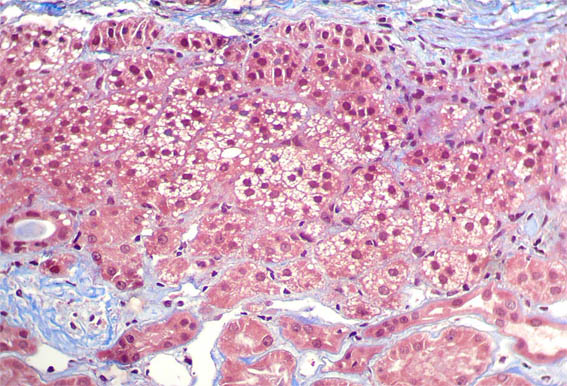

H&E, X100.

Figura 6. H&E, X200.

Figura 7.

Tricrómico de Masson, X200.